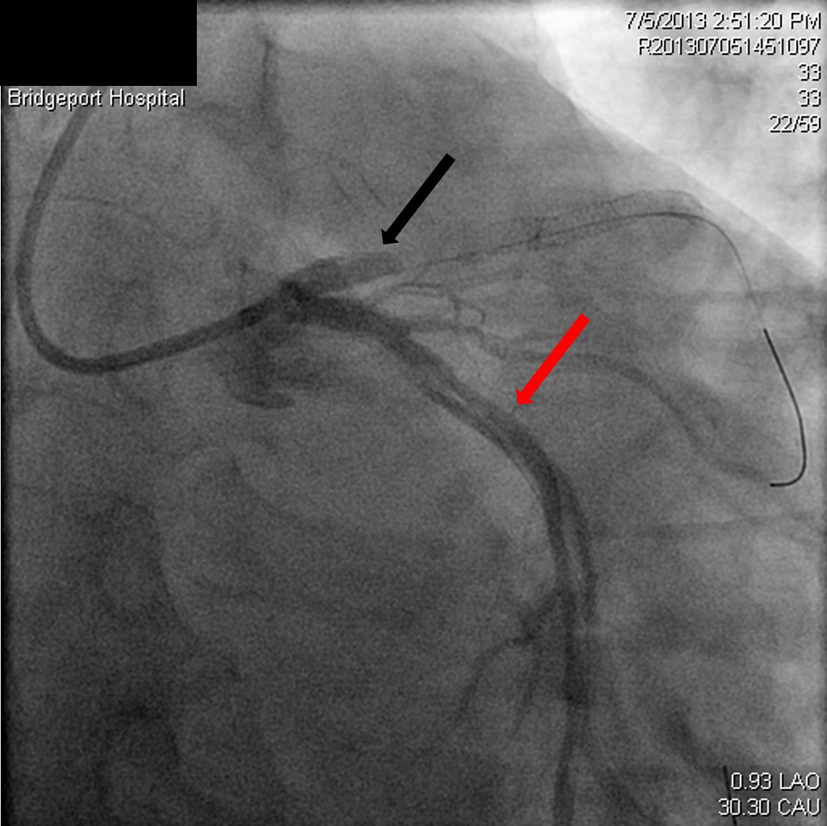

|  Click for large image | Figure 3. Spiral dissection of circumflex artery (red arrow), occluded LAD just prior to the stent (black arrow). |

|  Click for large image | Figure 4. Dissection extending into the aorta (red arrow), occluded LAD (black arrow). |

|  Click for large image | Figure 7. Restoration of flow in the circumflex artery (red arrow) and the LAD (black arrow). |